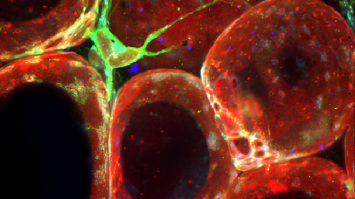

Experiment / VorführungZellmodelle in der AlternsforschungThema: GesundheitMit zunehmendem Alter steigt das Krankheitsrisiko durch altersbedingte Veränderungen im Körper und ungesunde Lebensstilfaktoren. Frühe Prävention und gesunde Gewohnheiten können das Risiko mindern. Mitochondrien-Dysfunktionen spielen eine wichtige Rolle beim Altern, indem sie Zellschäden verursachen und altersbedingte Krankheiten fördern können.Universität Innsbruck17:00 - 23:00